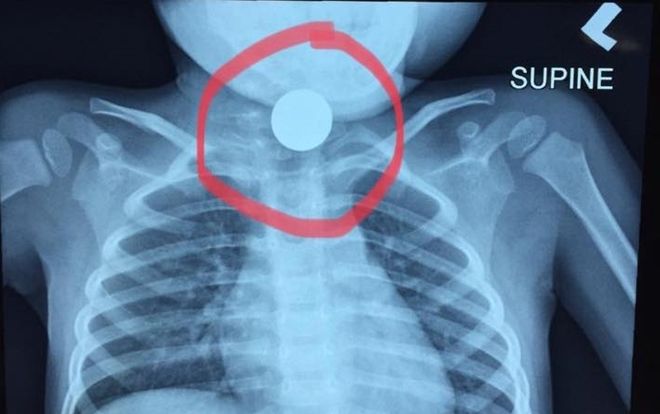

Mãi mê chơi đùa, bé gái 4 tuổi nuốt đồng xu phải nhập viện cấp cứu

Sau quá trình tiếp nhận, các bác sĩ của Bệnh viện Hoàn Mỹ Đà Nẵng đã tiến hành nội soi, gắp thành công dị vật là đồng xu bên trong dạ dày của một bệnh nhi 4 tuổi.

Sau quá trình tiếp nhận, các bác sĩ của Bệnh viện Hoàn Mỹ Đà Nẵng đã tiến hành nội soi, gắp thành công dị vật là đồng xu bên trong dạ dày của một bệnh nhi 4 tuổi.

Một bà mẹ người Malaysia mới đây đã chia sẻ lên Facebook cá nhân câu chuyện con trai cô nuốt phải tiền xu nhưng sự tắc trách của bệnh viện khi tuyên bố... hết chỗ khiến con cô phải chịu đau lâu hơn.